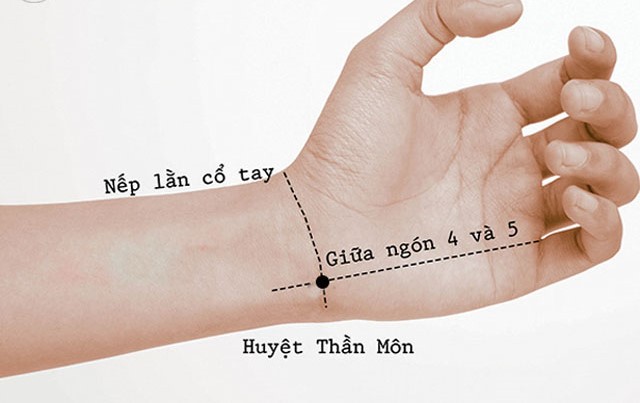

1. Huyệt thần môn

Vị trí: Trên cổ tay, phía bên trong, ngay dưới xương trụ.

Cách bấm: Dùng ngón cái ấn nhẹ vào huyệt trong 1-2 phút, kết hợp hít thở sâu.

Tác dụng: Giúp thư giãn thần kinh, giảm lo âu, cải thiện giấc ngủ.

- Bấm huyệt thần môn (nằm ngay cổ tay, phía trong) trong 1-2 phút, kết hợp hít thở sâu.

- Bấm huyệt thần môn, nội quan (ở mặt trước của cổ tay) bằng ngón cái trong 1 phút.